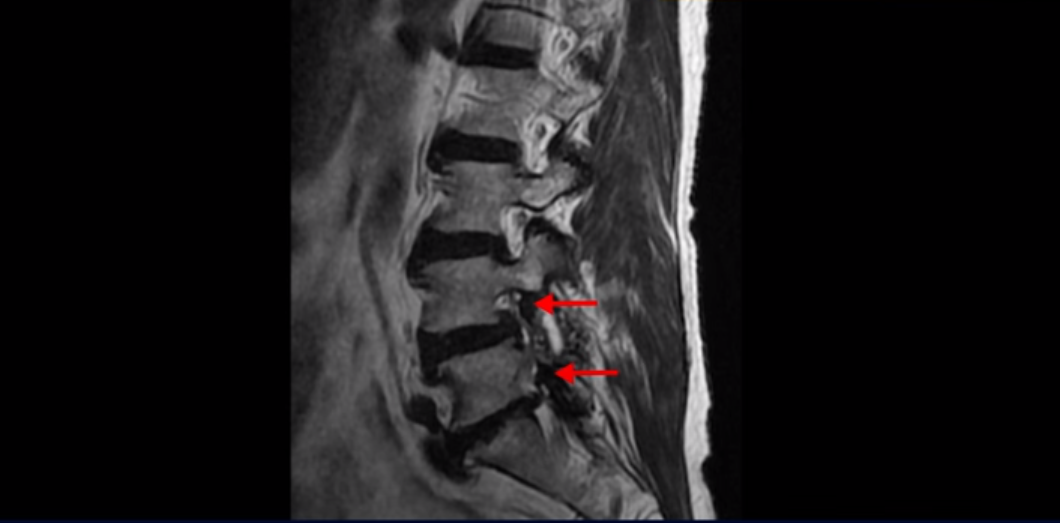

이분 MRI 보면서 설명드린 후 왜 이분처럼 발병한지 얼마 안된 협착증이 치료가 정말 빠르고 쉬운 건지 또 치료는 어떻게 하는 건지 자세히 설명 드리도록 하겠습니다.

MRI를 보면 척추 여러 마디가 퇴행되어 있고

척추관도 좁아져 있고

특히 왼쪽 신경가지가 빠져나가는 4번 5번, 5번 1번 추간공들이 많이 좁아져 있습니다.

그래서 이분은 몇 달 전부터 갑자기 왼쪽 엉덩이부터 발바닥까지 저리고 아픈 증상이 생겨서 걷기도 어렵고 무릎도 차고 시립니다. 그런데 왜 이렇게 얼마 전에 갑자기 발병한 협착증일수록 치료가 정말 빠르고 쉽다는 걸까요?

이분이 처음 아프게 된 건 작년 말입니다. 그런데 만일 이분이 아프기 전인 작년 초에 MRI를 찍었다면 지금 보시는 MRI와 많이 다를까요? 정답은 거의 차이가 없다입니다. 노화로 인해 신경 구멍이 좁아진 건 이미 오래 전에 벌어진 일입니다. 이렇게 신경 구멍이 좁아져 있는 채로 아무런 증상을 느끼지 않고 최소 5년에서 10년 이상 잘 산 것입니다. 이런 걸 잠복 협착이라고 합니다. MRI로 협착이 보이지만 아무런 증상이 없다는 뜻입니다.

그럼 왜 작년 말에 갑자기 아프게 된 걸까요? 바로 근육에 문제가 생겼기 때문입니다. 60세 넘어서 근육이 줄어들고 약해진 상태에서 무리한 일이나 운동 등으로 근육에 문제가 생기면 허리를 잘 지지하지 못하니까 신경이 자극되고 눌리는 증상이 생기는 겁니다. 신경 구멍이 좁아져 있으니까 근육에 문제가 생기면 신경 자극 증상이 더 쉽게 나타나는 겁니다. 이분은 영상에는 없지만 작년 겨울 스키를 타다 넘어졌다고 했습니다. 아마 그게 근육문제를 일으켰고 발병에 영향을 주었을 가능성이 높습니다.